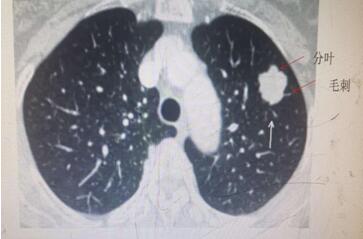

肺内结节,不容忽视,但也不必惊慌。肺部小结节并非一定就是肺癌,恶性肿瘤远少于良性病变。一般根据结节大小、形态并结合你的年龄与吸烟状况来分析。通常以下情况肺癌的可能性大:年龄在55岁以上;有慢性肺部疾病史和家族史的患者;肺部小结节直径>1厘米;边缘有毛刺和分叶;内部密度不均匀表现为实性结节或者混杂性结节。需要注意的是,有吸烟史的人,是肺癌的高危人群,年数乘以每天吸烟的支数>400支/年的吸烟患者患肺癌的几率会明显增高。